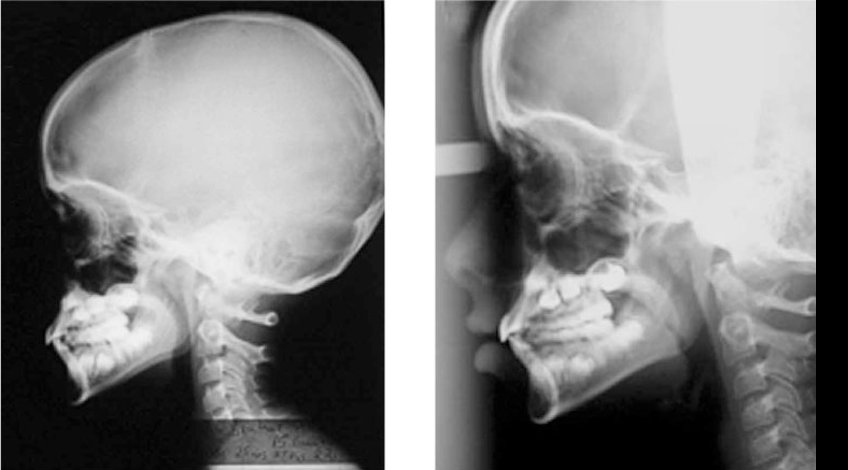

Radiografías, Imagenes de Cavum Rinofaringeo

El cavum es el techo de la faringe, situado en la nasofaringe, donde se encuentran las amígdalas faríngeas y las adenoides. Este examen también denominado RLC, en los estudios radiografía lateral de nasofaringe o de cuello, evalúa el tamaño del tejido adenoideo de la faringe y de las amígdalas palatinas y su eventual repercusión sobre la amplitud de la vía aérea. Su principal indicación es en el estudio de niños que respiran por la boca, y en aquellos con otitis media a repetición.

Las adenoides se hacen evidentes a los seis meses de vida y aumentan rápidamente durante los primeros 6 a 8 años.La ausencia de ésta en niños mayores de 6 meses sugiere una inmunodeficiencia.